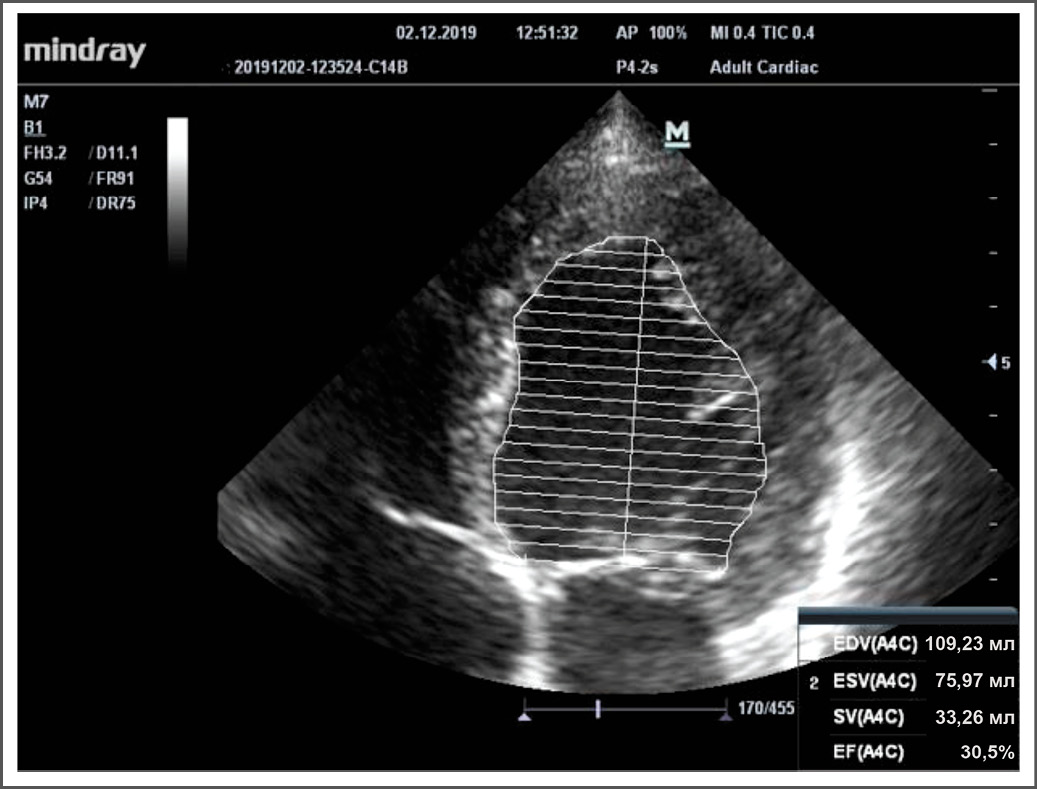

На момент прохождения химиотерапии, со слов пациентки, её рост составлял 160 см, масса тела – 68 кг, площадь поверхности тела – 1,56 м2. Ориентируясь на эти данные, мы ретроспективно рассчитали суммарную полученную дозу доксорубицина. Суммарная доза доксорубицина – 417,2 мг, что не превышает предельно допустимого суммарного уровня препарата. При обследовании пациентке была выполнена эхокардиография. Установлено выраженное снижение глобальной сократимости левого желудочка (фракция выброса по Симпсону – 30%) (рис. 1), выраженная эксцентрическая гипертрофия миокарда левого желудочка, дилатация всех камер сердца с формированием тяжёлой вторичной митральной (рис. 2) и трикуспидальной недостаточности, снижение сократимости свободной стенки правого желудочка (амплитуда систолического движения кольца трикуспидального клапана, TAPSE – 1,5 см), дилатация лёгочной артерии и нижней полой вены и признаки тяжёлой легочной гипертензии.

Рис. 1. Эхокардиографическое исследование пациентки Д.Н. Верхушечное ٤-х камерное сечение (значительное снижение фракции выброса по Симпсону).

Примечание (здесь и на рис. 3). EDV – конечно-диастолический объём, ESV – конечно-систолический объём, SV – ударный объём, EF – фракция выброса, A4C – верхушечное 4-х камерное сечение.

Fig. 1. Echocardiography of patient D.N. Apical ٤-chamber section (significant reduction in Simpson's ejection fraction).

Note (here and in Fig. 3). EDV – end-diastolic volume, ESV – end-systolic volume, SV – stroke volume SV, EF – ejection fraction, A4C – Apical 4 chamber section.